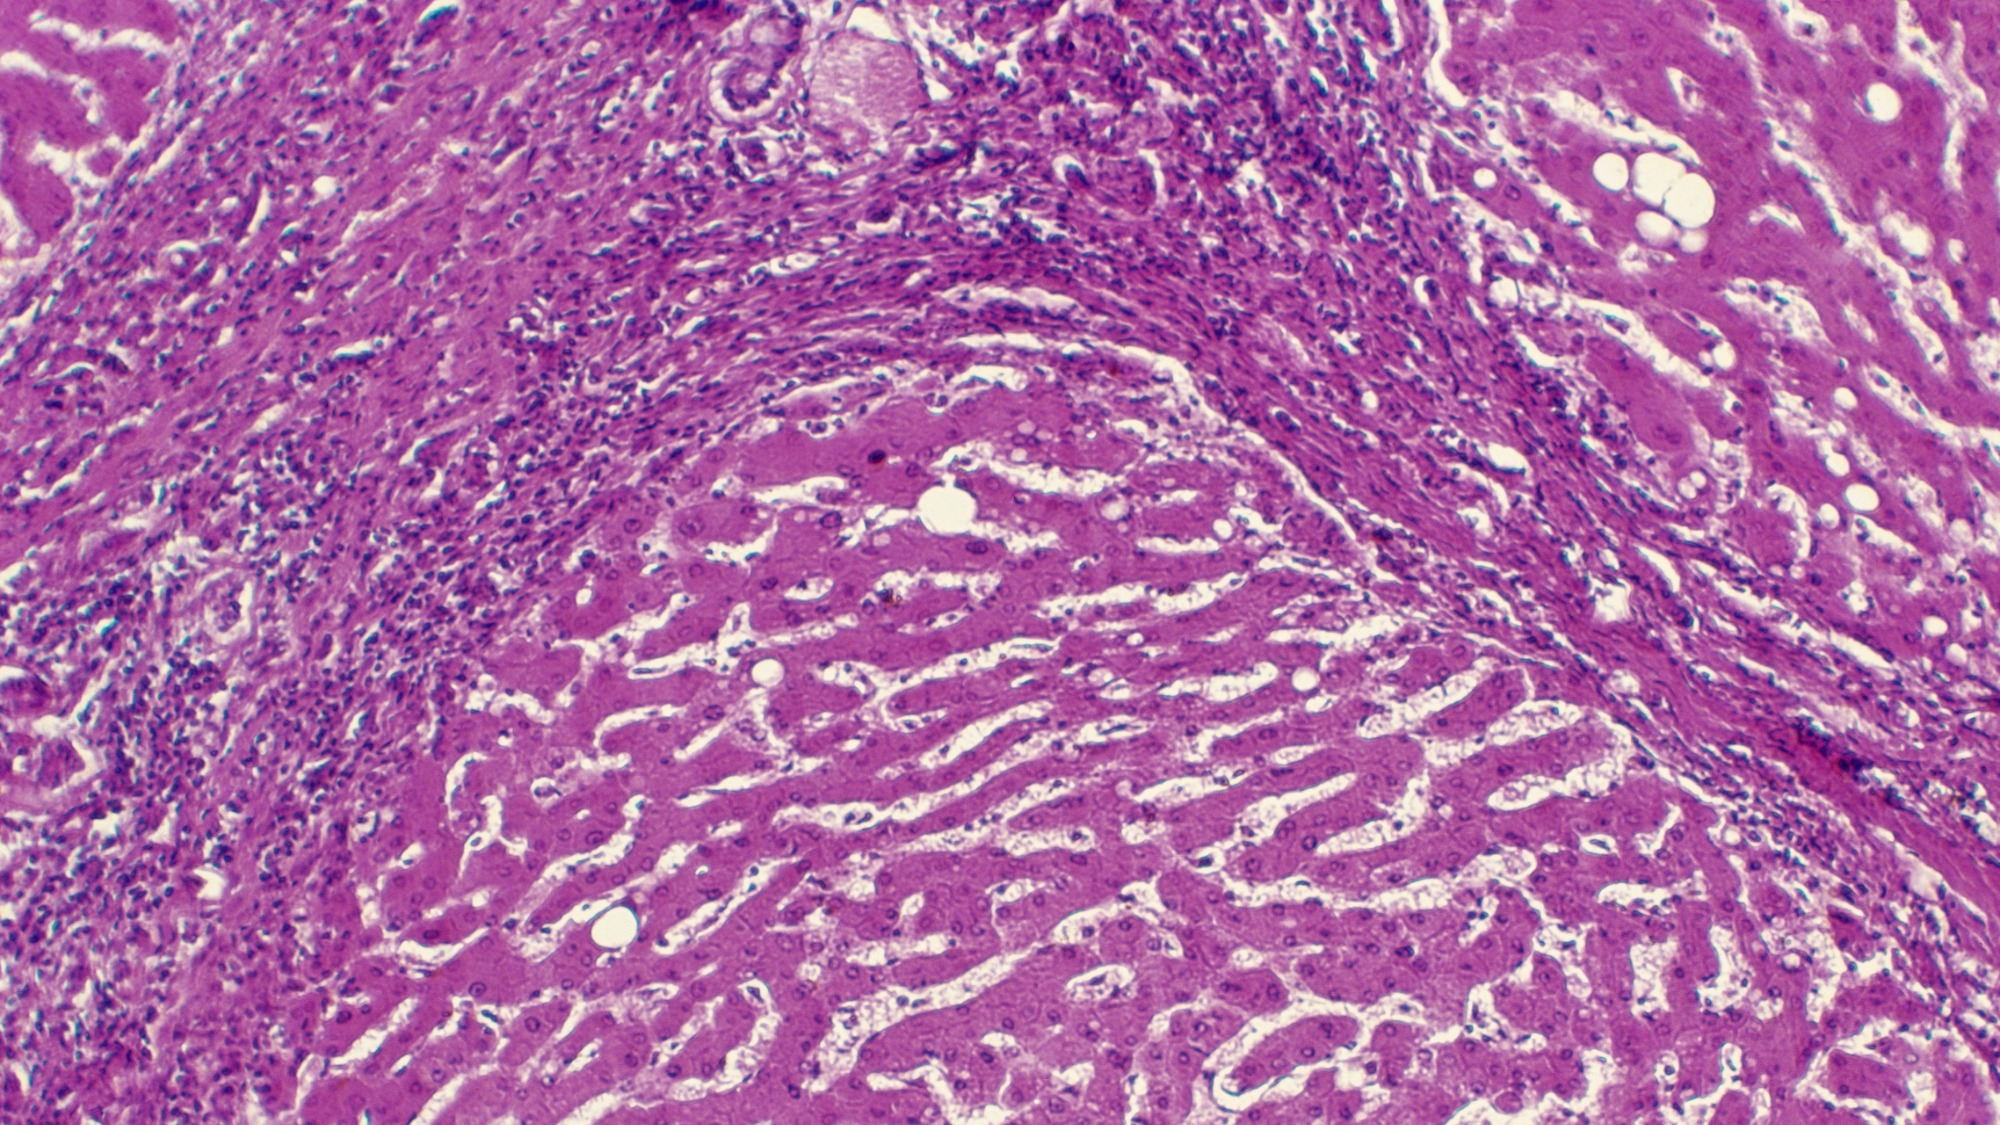

Histology image of the liver in a case of cirrhosis of the liver from alcoholism.

Histology image of the liver in a case of cirrhosis of the liver from alcoholism. Alcoholic liver disease is the most common cause of alcohol-induced deaths nationally. Photo by DeAgostini/Getty Images